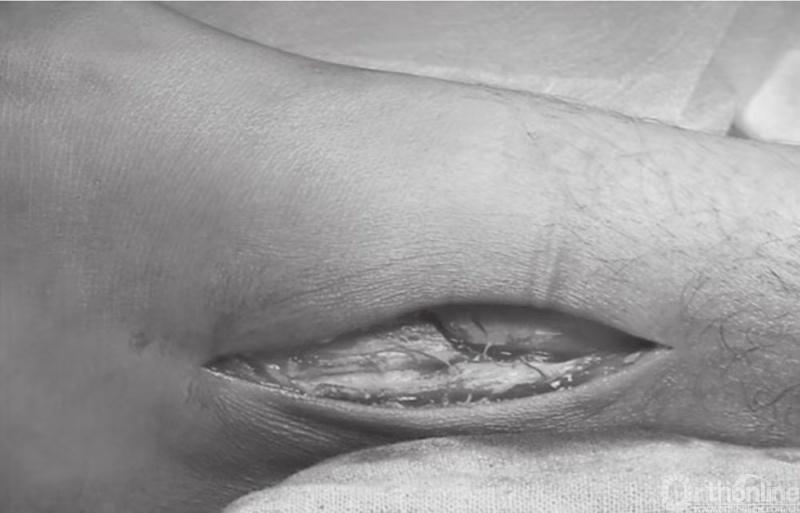

为避免神经瘤的形成,穿过腓骨远端的腓浅神经应得到保护。切开皮肤后,沿着切口线分开深筋膜(图3)。

图3 切开皮肤后,沿着切口线分开深筋膜